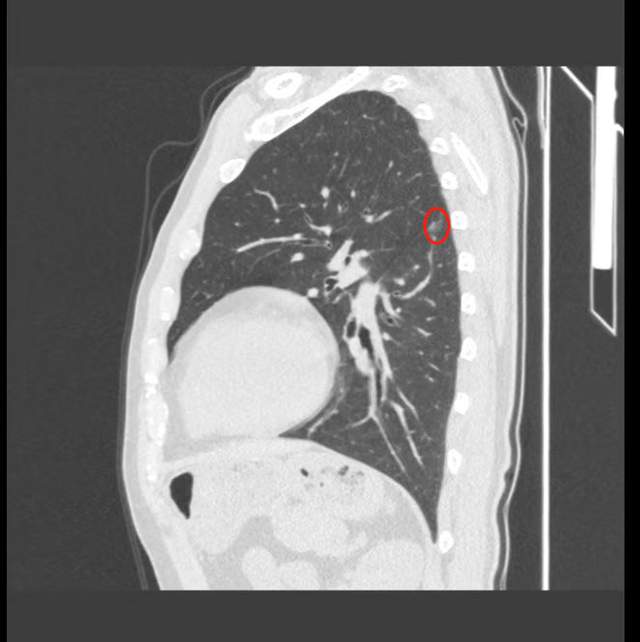

两年前,王伯伯在体检中偶然发现左下肺部存在一个结节。此后,他一直在常德市四医院肺结节门诊接受定期随访。主任医师肖炳华及其团队接诊后,对患者进行了全面细致的评估。经过近两年的观察,发现左下肺背段的部分实性结节增大至1.5cm,被判定为高风险结节。基于这一评估结果,肖炳华建议患者尽快进行手术治疗。

入院后,医疗团队利用CT三维影像重建技术,精确定位了结节所在位置——左下肺背段。在此基础上,团队进行了详尽的影像学评估和手术规划,以确保手术的精准性和安全性。

2025年2月中旬,常德市四医院胸外科医师团队成功为王伯伯实施了胸腔镜下左下肺背段a+b亚段切除术。术中,病理报告显示该结节为微浸润性腺癌,且淋巴结均未发现癌转移。整个手术过程流畅高效,出血量极少,成功达到了根治的目的。术后,患者无需进行抗肿瘤治疗。